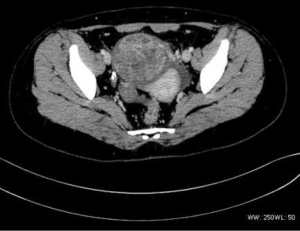

There were nine cases of cervical tumors, and one case of uterine body lesions. Two cases involved tumors that were limited to the local cervix, seven cases involved invasion to the lower part of the uterine body or vagina, two cases had lung and liver metastasis, and one case had pelvic and retroperitoneal lymph node metastasis.

There were two bladder tumor cases, which included one case with infiltrative growth and slight enhancement, and one multiple-onset case with lobulated mass, obvious enhancement, and lumbar and bilateral adrenal metastasis. Both cases had pelvic lymph node metastasis.